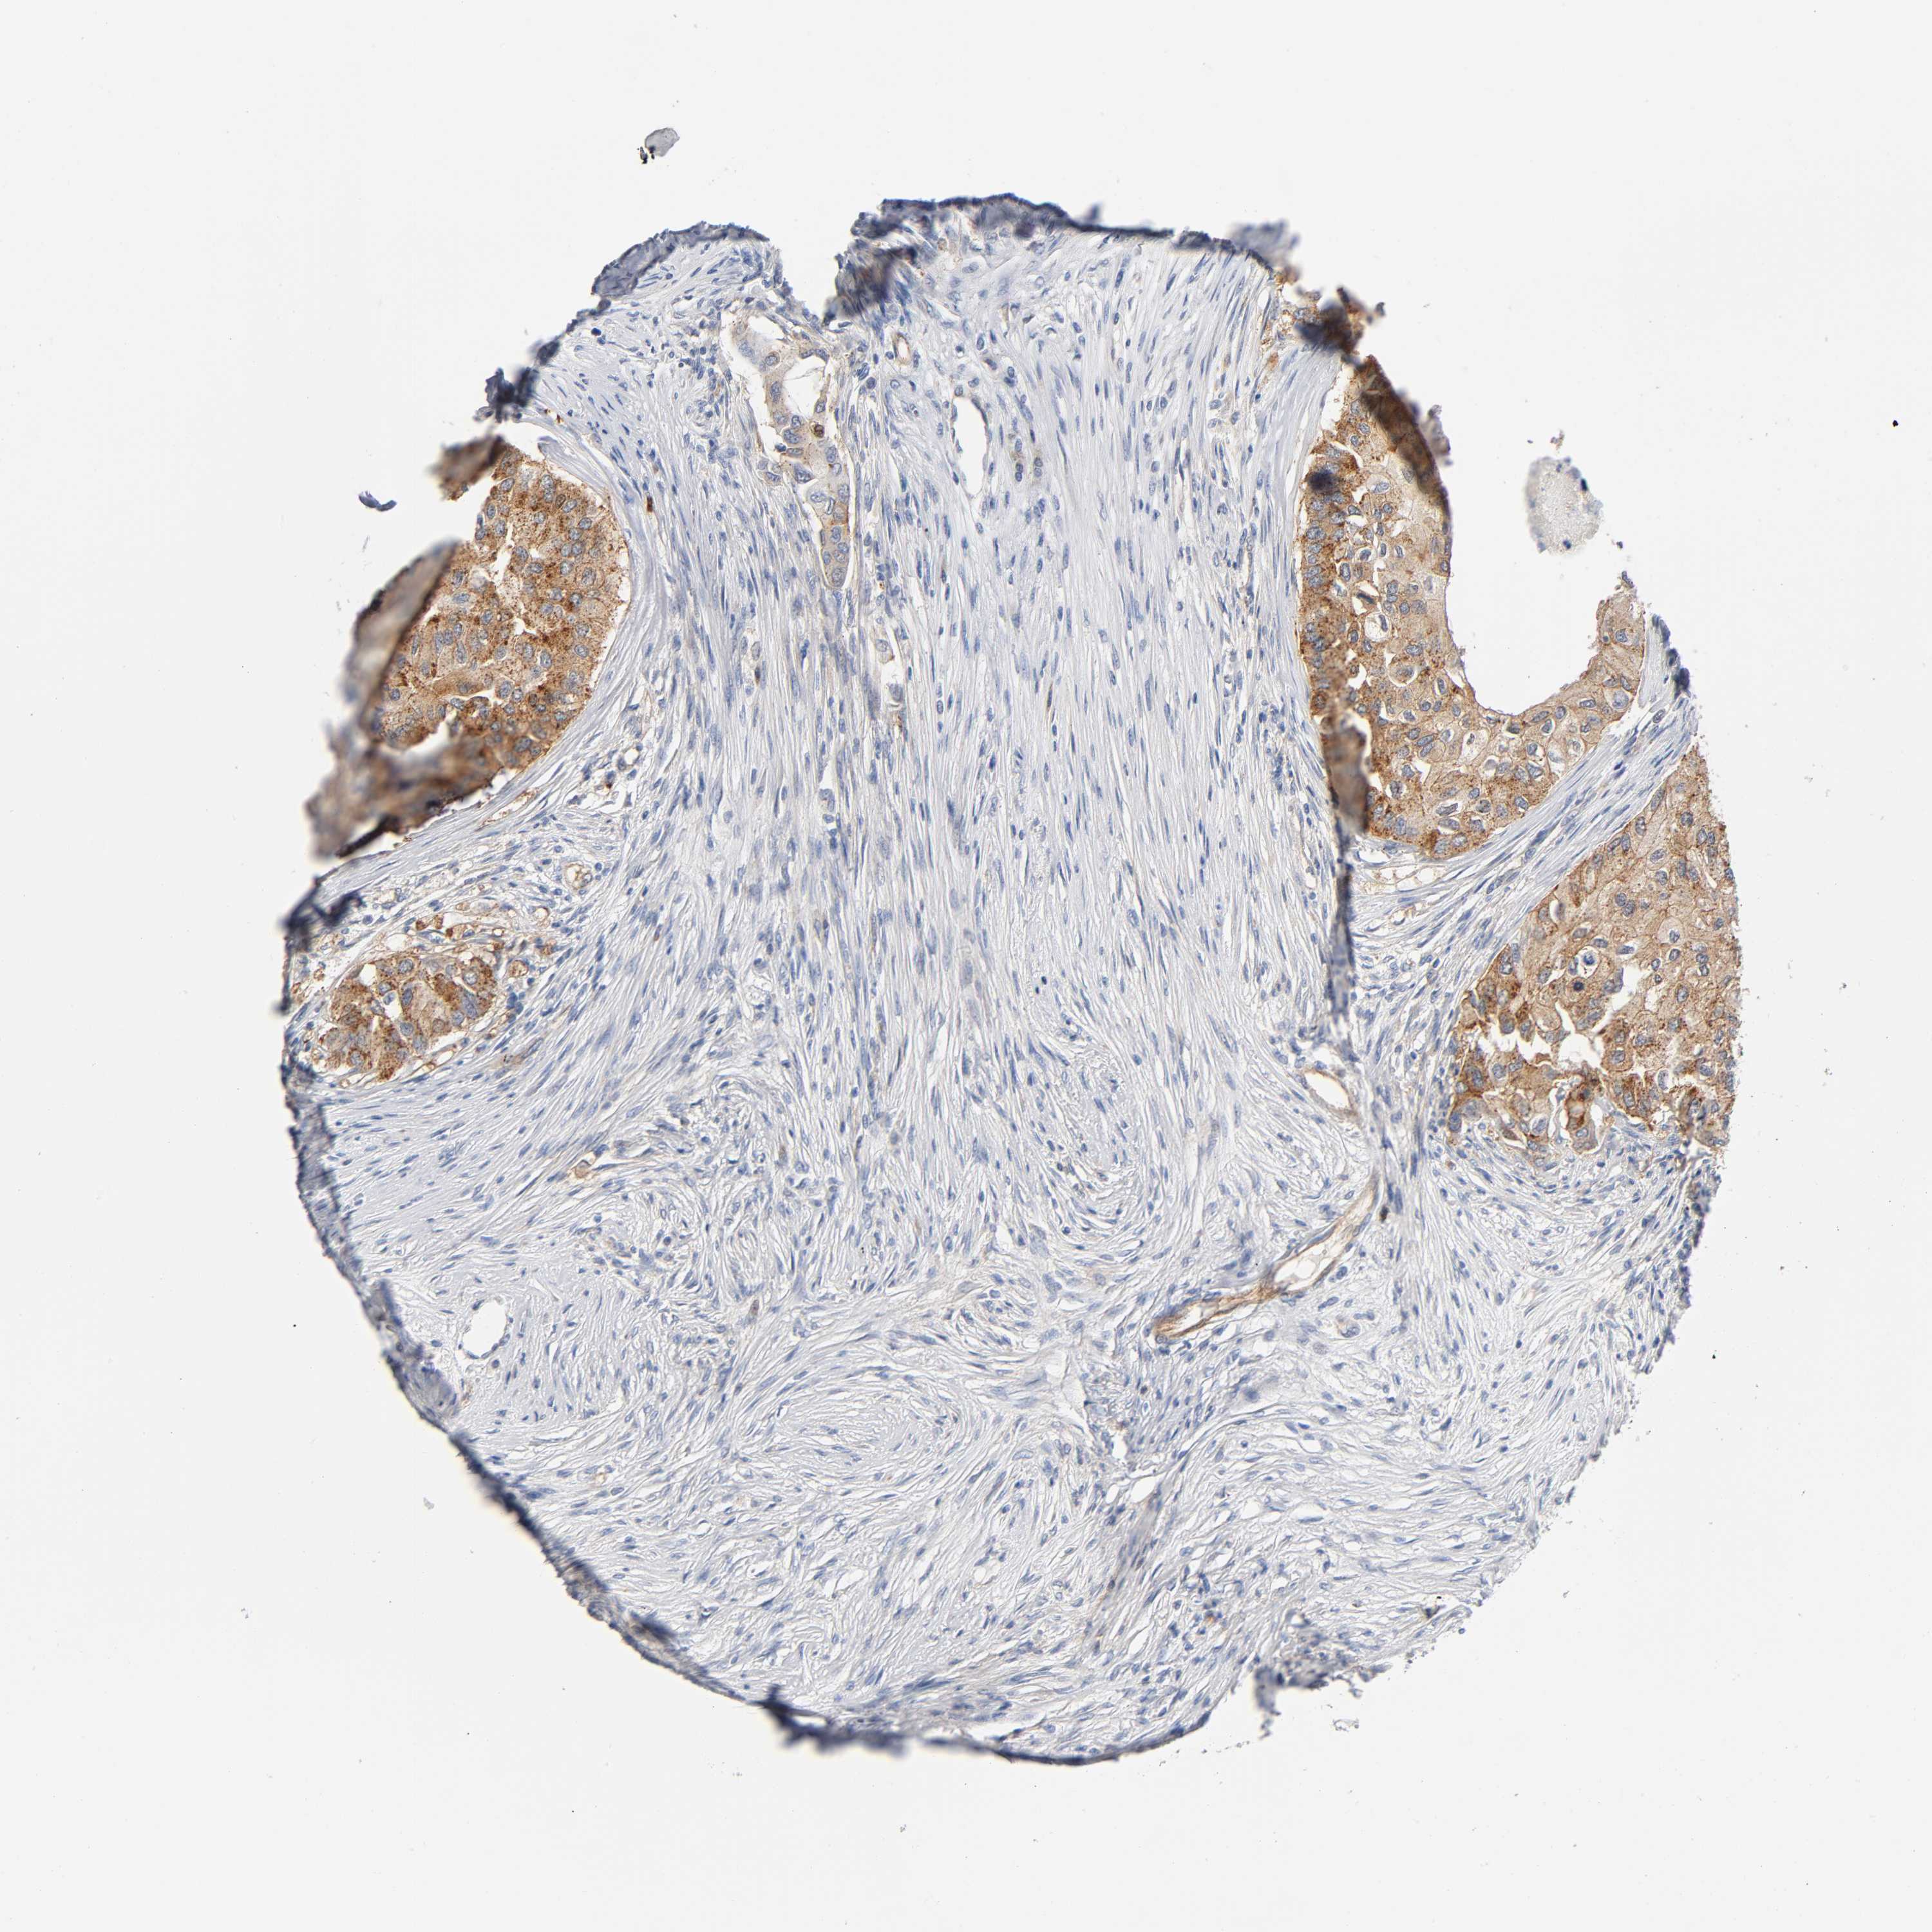

CANCER BREAST CANCER Show tissue menu

BRCA TCGA BRCA VALIDATION PROTEIN EXPRESSION

Breast cancer

Human cancer